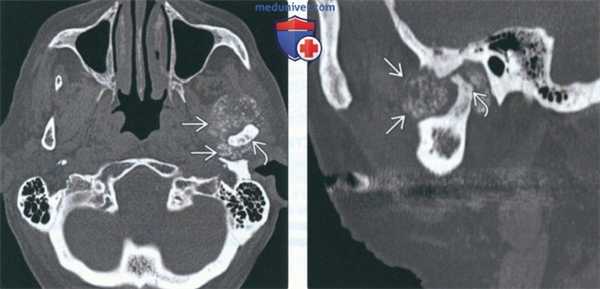

(Слева) На аксиальной КТ в костном окне визуализируется типичная хондросаркома ВНЧС с множественными кальцинатами. Мыщелок нижней челюсти слева неравномерно склерозирован, в ВНЧС и вокруг него визуализируются множественные мелкие очаговые кальцинаты.

(Справа) На сагиттальной реформатированной КТ у этого же пациента определяется деформация мыщелка. Некоторые кальцинаты, вероятно, находятся в мягкотканном компоненте за пределами сустава.

(Слева) КТ в костном окне, аксиальная проекция. Типичная хондросаркома левого височно-нижнечелюстного суаава. Мыщелок нижней челюсти склерозирован и имеет неправильную форму, внутри и вокруг сустава рассеянны множественные кальцификаты. И хотя в данном случае достаточно сложно дифференцировать заболевание от синовиального хондроматоза, в обоих случаях лечение должно быть хирургическим, а точный диагноз будет установлен после гистологического исследования.

(Справа) Реконструкция в сагиттальной плоскости, этот же пациент. Мыщелок деформирован, а часть кальцификатов находится в мягких тканях вне сустава.